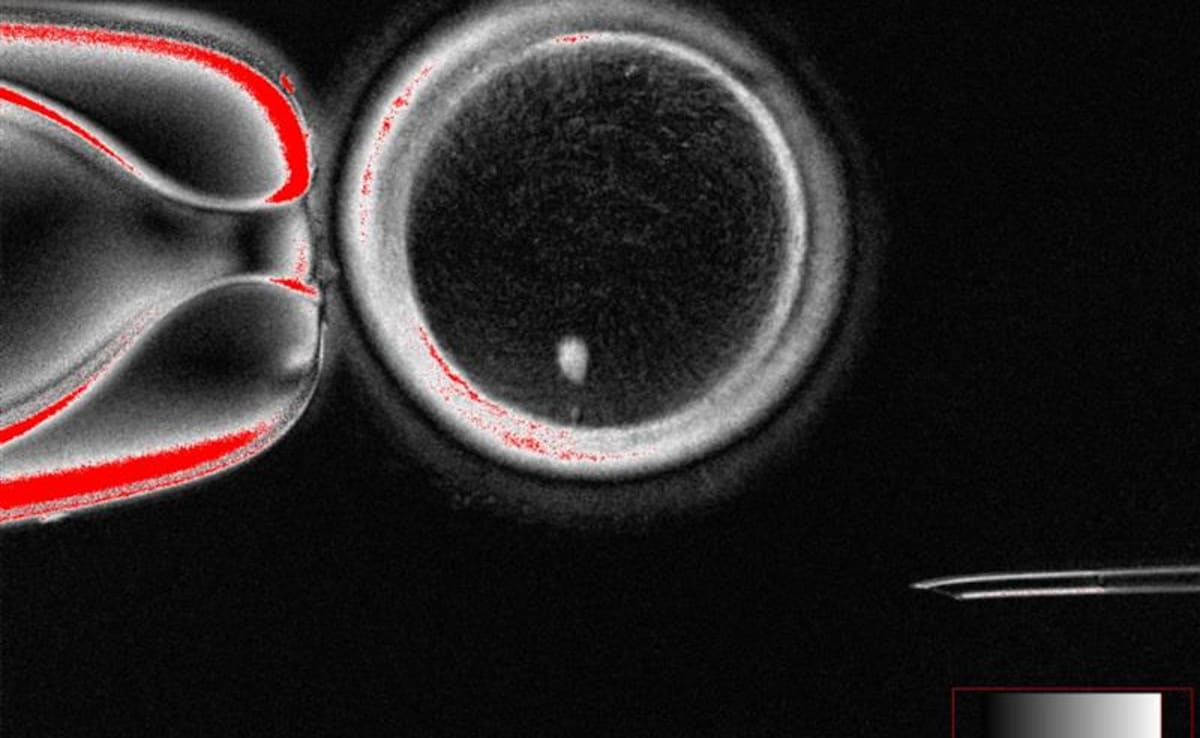

Scientists said Tuesday they have turned human skin cells into eggs and fertilised them with sperm in the lab for the first time — a breakthrough that is hoped to one day let infertile people have children.

Scientists said Tuesday they have turned human skin cells into eggs and fertilised them with sperm in the lab for the first time — a breakthrough that is hoped to one day let infertile people have children.